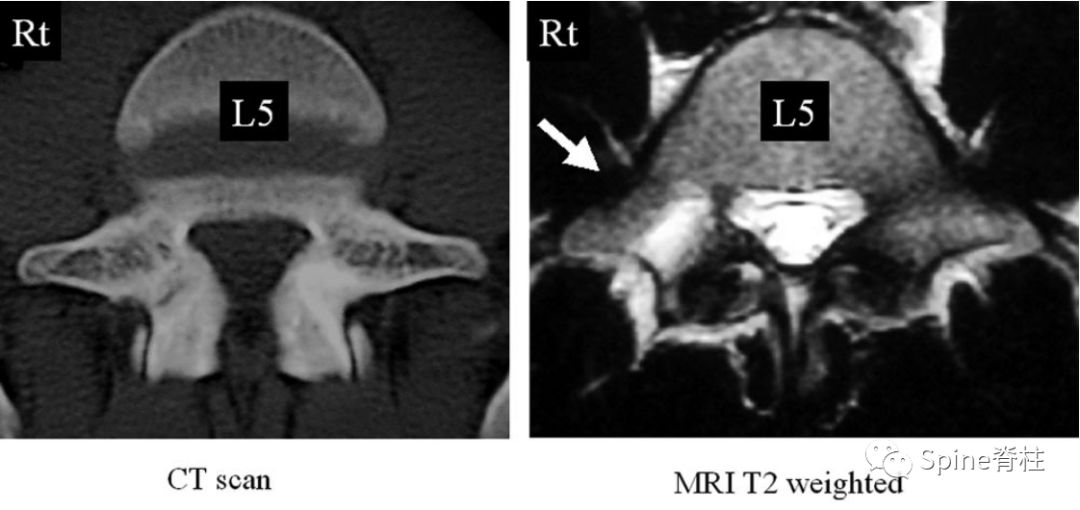

左侧为椎弓根水肿阳性,右侧为椎弓根水肿阴性,有研究发现峡部裂伴随着椎弓根水肿,支具固定愈合率更高

左侧早期峡部裂伴椎弓根水肿,支具固定6月后愈合

右图提示椎弓根高信号改变(箭头)

右图:右侧椎弓根高信号改变明显,左侧椎弓根轻微高信号